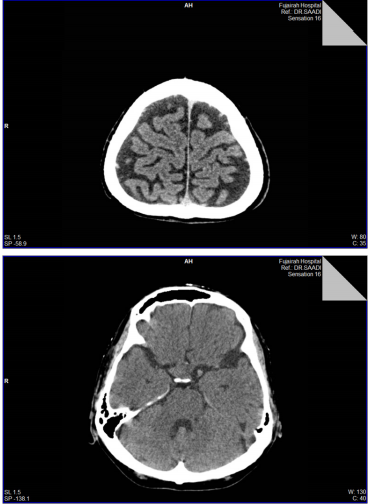

3. Urgent CT of head was performed and reported as: An ill-defined soft tissue density lesion in the supra-sellar region with possible sellar extension, No intracranial hemorrhage, or edema, no midline shift.., MRI is recommended with contrast for better delineation of this lesion... (MRI was not feasible because of Patient’ clinical status!)

2. CT Head & Sinuseswas taken and reported: there is no middle line shift, no edema or signs of inflammations, same previous findings...

1. Based on the detailed history given by Dr. AlJadir, both CT and MRI images of the pituitary were reviewed.

2. CTHead showed a dense enlarged pituitary gland with a hyperdense area on its right side consistent with hemorrhage…

CT- head nov. 20

1. The hyper density noted in the Pituitary Gland in the previous studies resolved completely, indicating that there is no fresh hemorrhage …

2. Normal brain parenchyma and ventricular system, normal cerebral sulci and basal cistern…